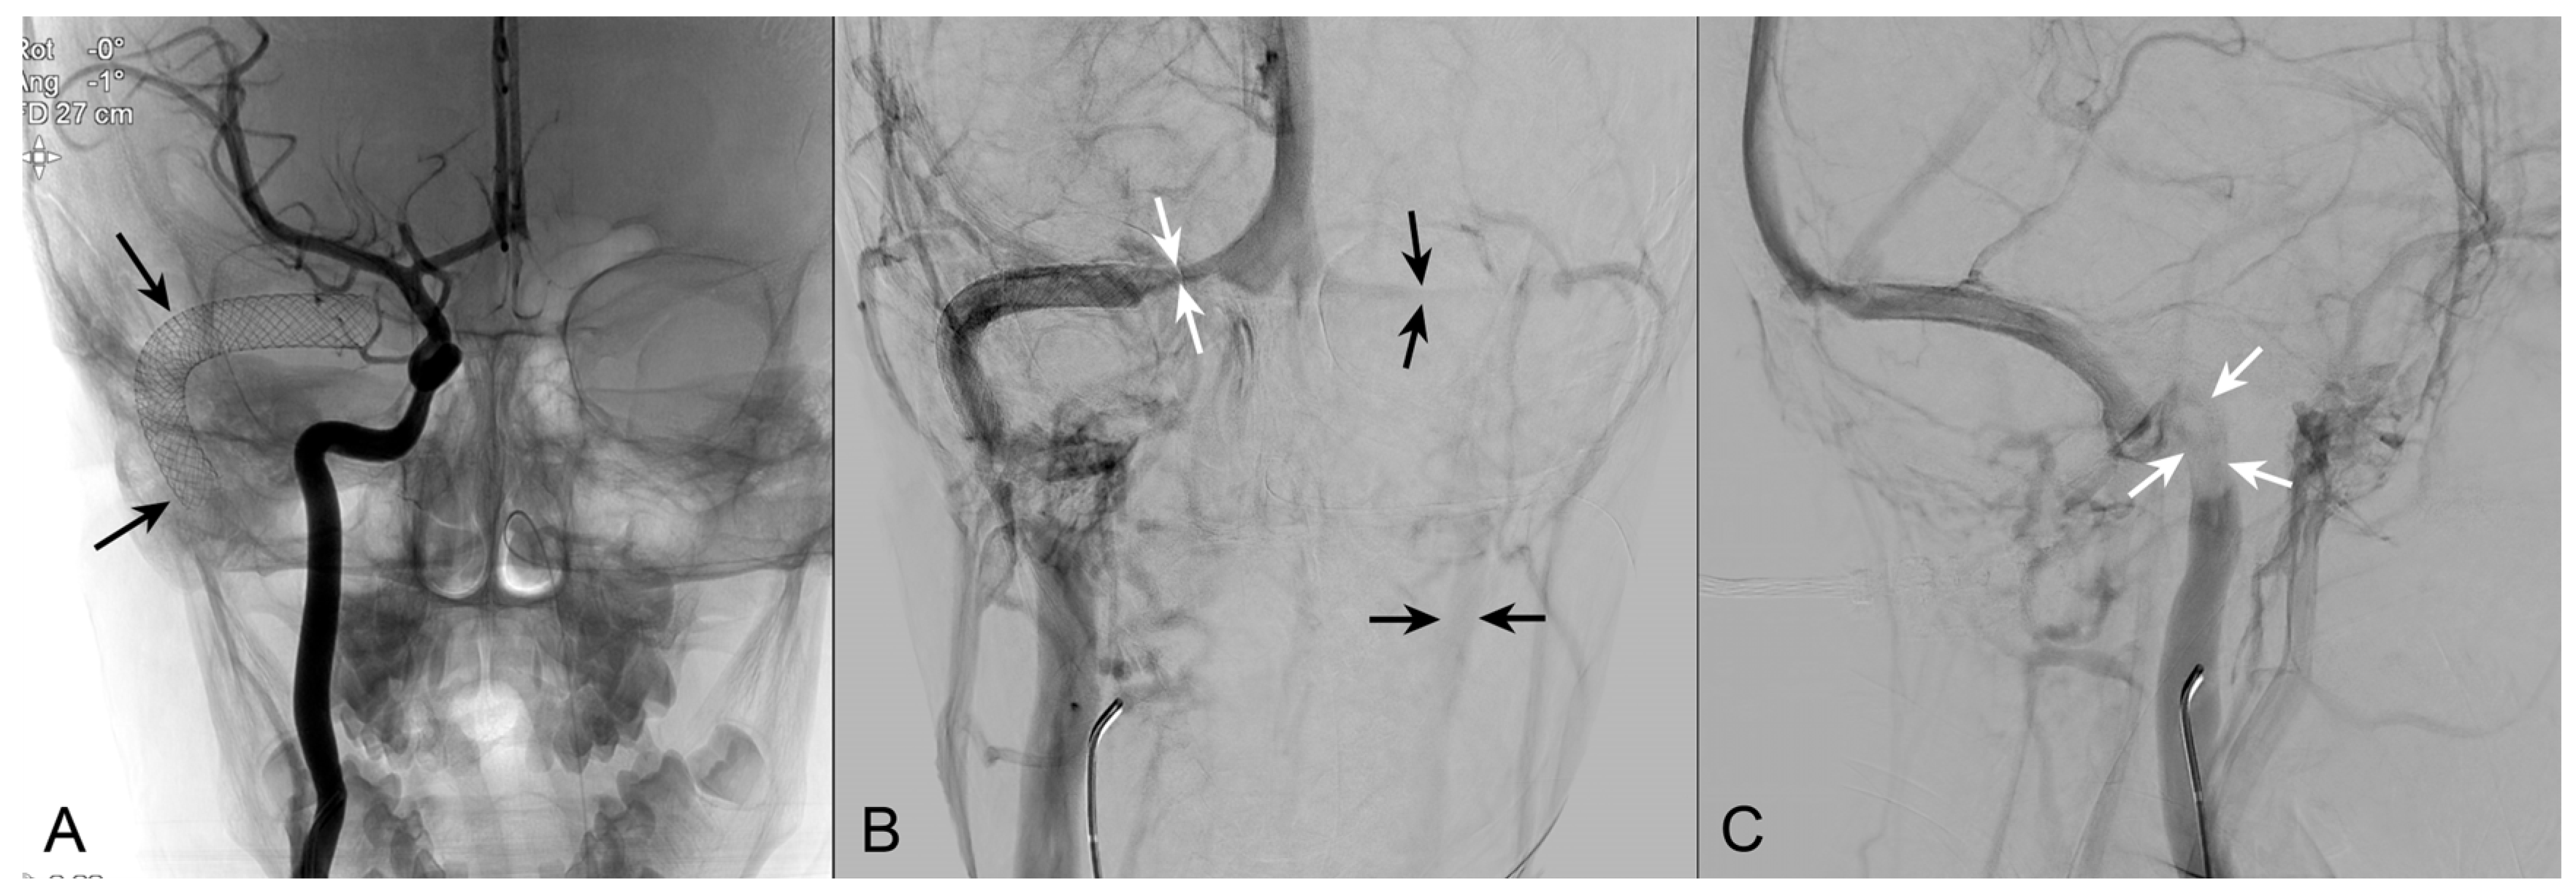

3.1. Case Report